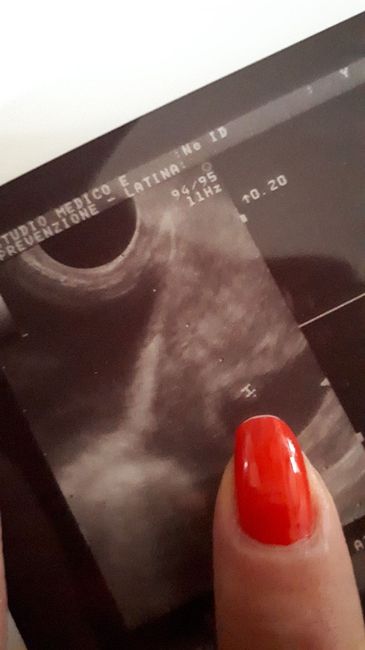

Sono di quasi 7 settimane ,l altro ieri sono stata per l eco dalla ginecologa e inizialmente mi fece molto preoccupare in quanto mi disse che c era solo il nido senza l...